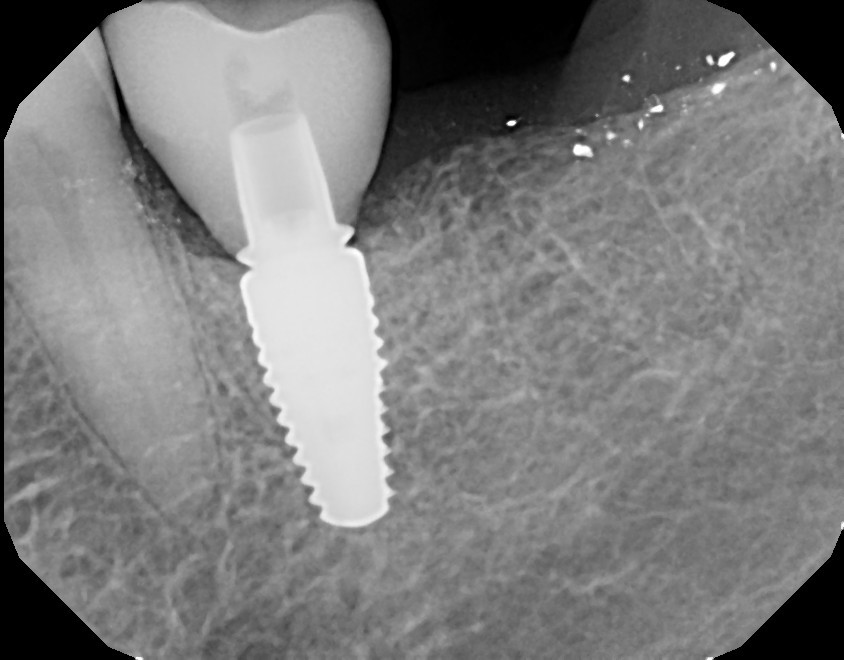

Fig 13. A custom healing abutment was created to replicate the emergence profile for a mandibular molar, which is square in cross-section.

Figure 13

Fig 14. A periapical radiograph of the custom healing abutment on the implant demonstrated the development of a natural emergence profile for a mandibular molar to replicate the missing natural tooth.

Figure 14